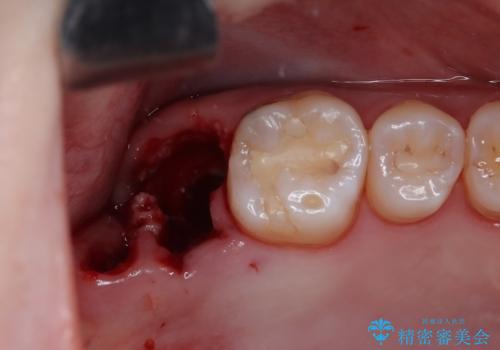

右上のインプラント治療は、1DAYインプラント治療(抜歯即時埋入・即時荷重)の適応となりましたので、通常3回必要な外科処置の回数を1回に集約させることができました。

口腔内の環境が大きく改善し、現在はご自身のプラークコントロールにより良い状態が維持できるようになりました。